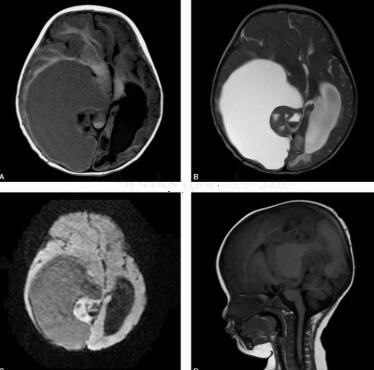

图1 右侧大脑半球深部脑实质内可见一巨大囊实性占位,大小约9.4cm×11.4cm×9.6cm,以囊性病变为主伴局部边缘实质性病变,囊性部分呈稍长T1、长T2信号,实性部分等信号,病灶内可见多个小囊状长T1、长T2信号灶。增强扫描实性部分明显强化,囊性部分及多发小囊性灶无强化。病变占位效应明显,右侧颞顶叶脑实质受压变薄,右侧侧脑室、第三脑室明显受压,左侧侧脑室扩大,左侧脑室旁见晕状长T1、长T2信号影。小脑半球未见明显异常。中线结构明显左移

右侧颞顶叶室管膜母细胞瘤(原始神经外胚叶肿瘤)(图2)

二、影像学表现

MRI在诊断幕上原始神经外胚层瘤具有重要价值。MRI对软组织具有良好的分辨率,无骨骼伪影干扰,尤其对PNET侵犯邻近结构及其范围显示十分清楚。幕上原始神经外胚层肿瘤的MRI表现依部位不同而变化。PNET多发生于脑叶深部位置,肿瘤体积常较大。与其他常见的颅内肿瘤相比,PNET在MRI平扫T1WI信号相对更低,T2WI信号更高,信号更不均匀。肿瘤的实质部分为T1WI等或略低信号区、T2WI信号强度较高。由于肿瘤生长较快,其内部常伴有囊变和坏死区,表现为T1WI明显低信号、T2WI明显高信号。囊变和坏死区并不局限于肿瘤中央部,而是在瘤体内呈灶状散在分布,亦可见于肿瘤边缘。部分病例肿瘤内可发生出血,在T1WI上表现为高信号。有时病灶内可见代表钙化和含铁血黄素的低信号区。虽然PNET是高度恶性的肿瘤,呈浸润性生长,但肿瘤边界清楚,虽然占位效应明显,但不伴或只伴有轻度瘤周水肿,在引起梗阻性脑积水后常可见明显的脑室旁间质性脑水肿。增强后扫描肿瘤实质部分呈明显强化,囊变和坏死区无强化。